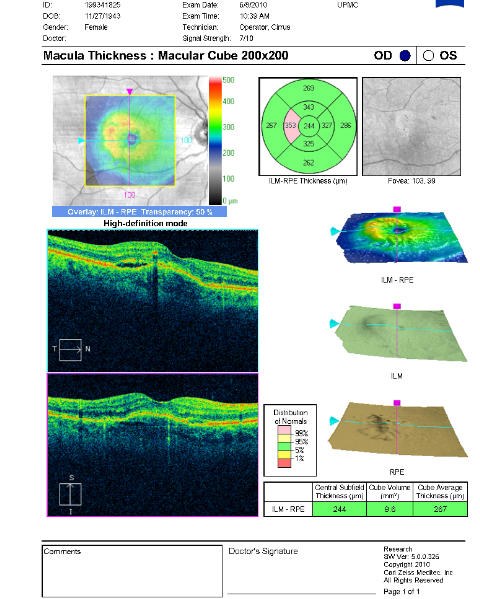

FUNDUS DESCRIPTION: |

OD OS |

OD Red-Free: Pre-Injection: Arterial: A-V: Venous: Recirculation: Late:

OS Red-Free: Venous: Recirc: Late:

Impression